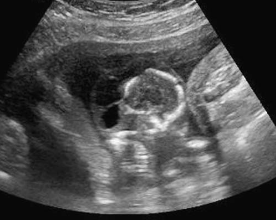

The sonographic finding in this image is most suspicious for:

ventriculomegaly